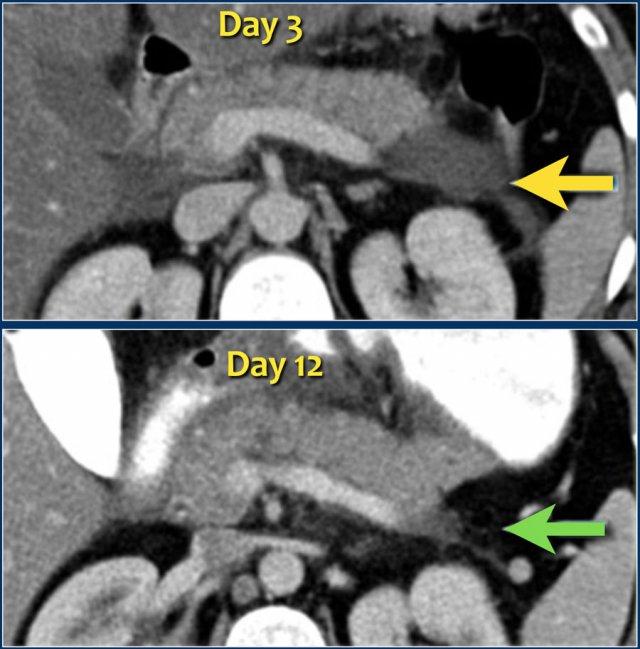

Trường hợp này là ví dụ điển hình của hoại tử tụy nhiễm trùng.

- Vào ngày thứ 1, tụy ngấm thuốc bình thường và hình ảnh chỉ giống như viêm tụy thể phù nề kẽ nhẹ.

- Vào ngày thứ 3, tụy không ngấm thuốc, phù hợp với hoại tử.

Hoại tử cũng liên quan đến mô quanh tụy.

Đây là ANC – ổ hoại tử cấp tính. - Vào ngày thứ 17, có các bóng khí trong ổ hoại tử phù hợp với hoại tử tụy và quanh tụy nhiễm trùng.

Ổ hoại tử được bao quanh bởi một thành.